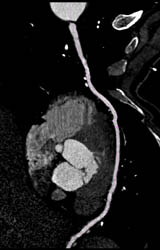

Diagnosis

Normal Circumflex